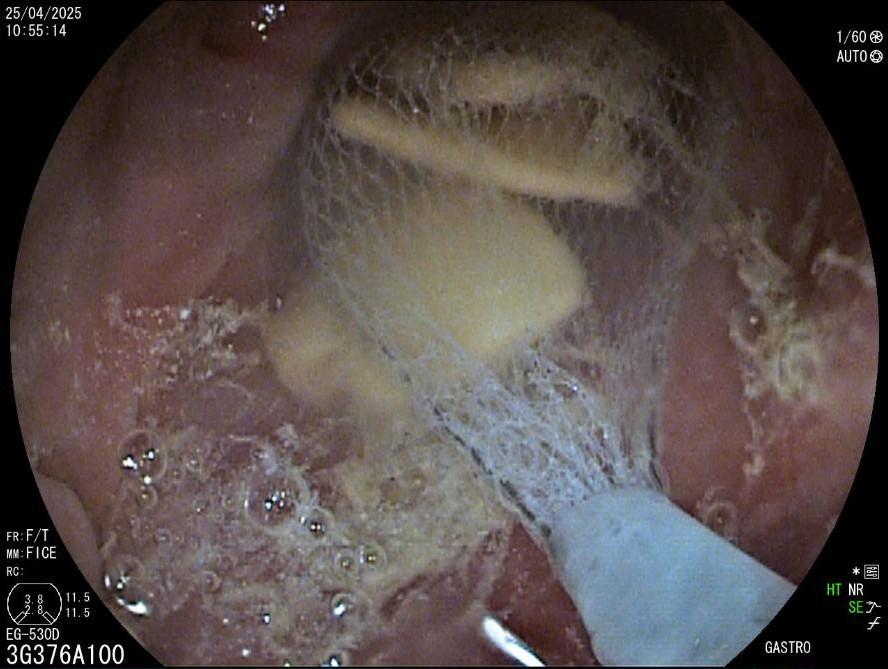

La evaluación endoscópica reveló un divertículo de Zenker de 3 cm, con retención significativa y acumulación de saliva y restos de comida (fig. 1). Se consideró que el paciente no era apto para la cirugía y se planificó una septotomía endoscópica.